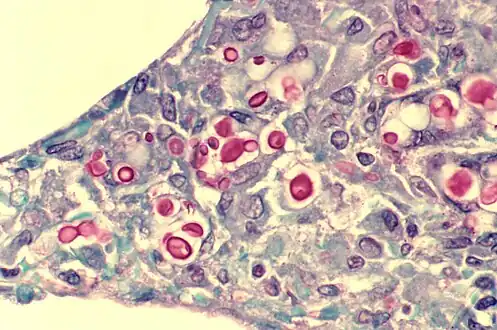

A histologic slide of a human alveolar sac

There are three major types of alveolar cell. Two types are pneumocytes or pneumonocytes known as type I and type II cells found in the alveolar wall, and a large phagocytic cell known as an alveolar macrophage that moves about in the lumens of the alveoli, and in the connective tissue between them. Type I cells, also called type I pneumocytes, or type I alveolar cells, are squamous, thin and flat and form the structure of the alveoli. Type II cells, also called type II pneumocytes or type II alveolar cells, release pulmonary surfactant to lower surface tension, and can also differentiate to replace damaged type I cells.[12][15]

Cryptococcosis of lung in patient with AIDS. Mucicarmine stain. Histopathology of lung shows widened alveolar septum containing a few inflammatory cells and numerous yeasts of Cryptococcus neoformans. The inner layer of the yeast capsule stain red.